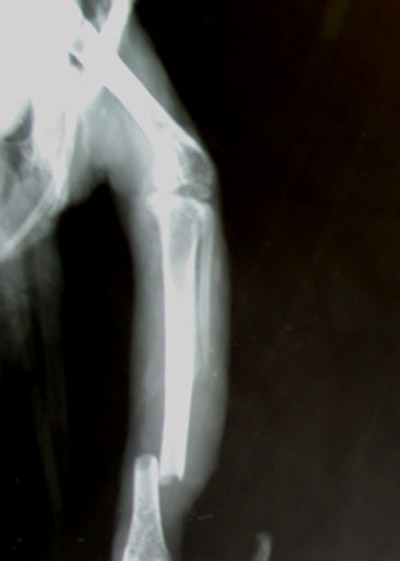

Papagei mit Marknagelung des Tibiotarsus und Meerschwein mit Unterschenkelfraktur